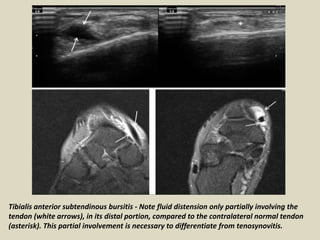

Tibialis anterior subtendinous bursitis - Note fluid distension only partially involving the

tendon (white arrows), in its distal portion, compared to the contralateral normal tendon

(asterisk). This partial involvement is necessary to differentiate from tenosynovitis.